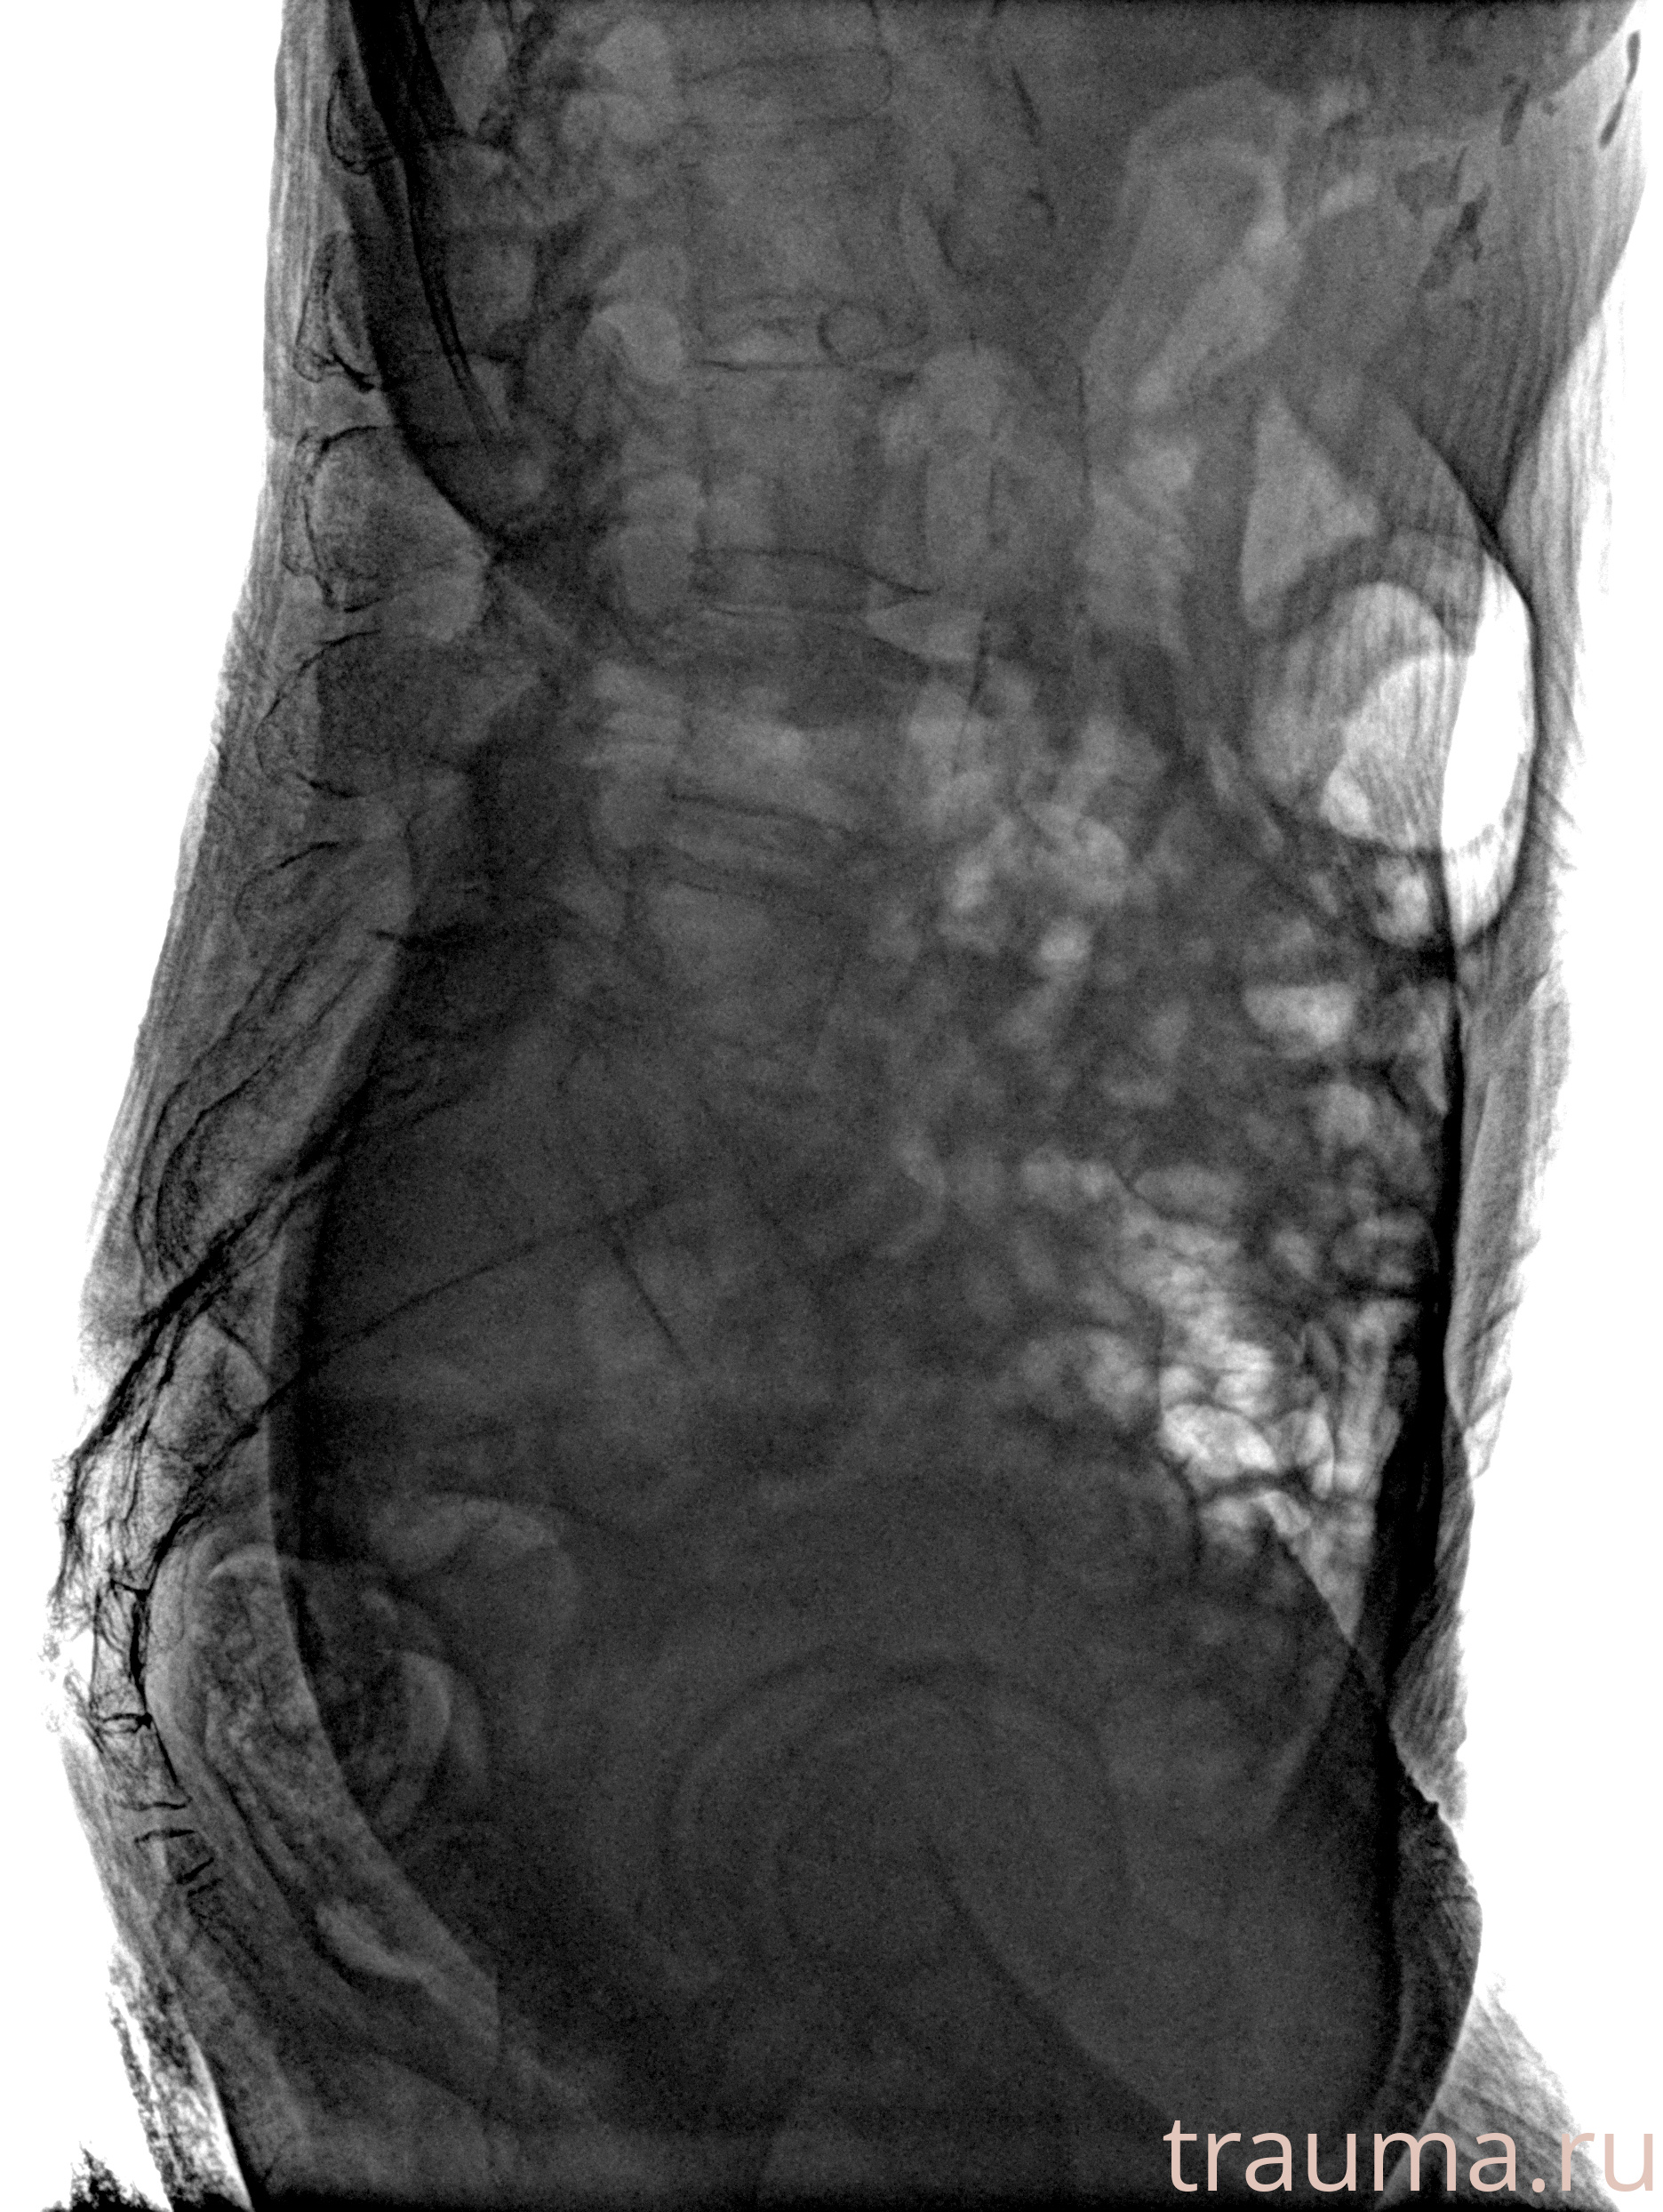

Рентген на дому: по вашему адресу приезжает врач-рентгенолог, травматолог-ортопед с мобильным рентгеновским аппаратом, проводит диагностику травмы или заболевания, делает необходимые рентгенограммы, дает рекомендации по дальнейшему лечению. Получить качественные снимки в домашних условиях возможно благодаря уникальной методике, разработанной МосРентген Центром для института  Склифосовского